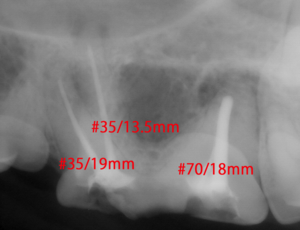

各々の根管にファイルを挿入し根管長を測定

ポータブルレントゲンによる術中写真

術後の写真 充填( 赤ラインは根先部 )

下記に5つの例を記載してみました。5kg / 20kg / 10kg / 5kg / 5kg

ISO 35 16mm / ISO 35 11mm / ISO 70 15.5mm